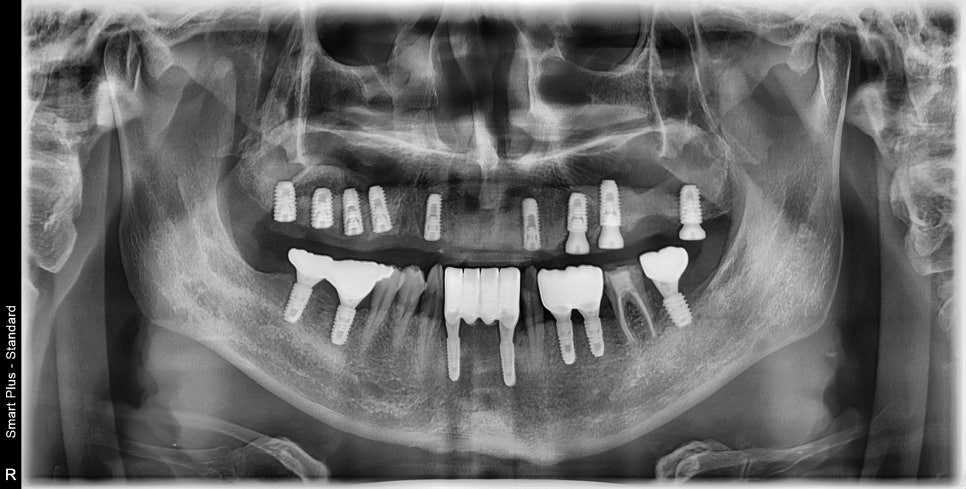

희색선=남아있는 치조골, 빨간원=상악동공간

어금니가 장기간 동안 상실된 상태이셨고

앞니 쪽으로 식사를 주로 하시다 보니

치주가 안 좋은 곳은 동요도가 심한 상태였습니다.

진단을 하기 전에 상악동 공간에 뿌옇게

염증소견이 보였습니다.

CT상에서 회색으로 보이는 공간은

만성비염에 의해 점막의 비후는 물론이고

염증이 차 있는 것을 볼 수 있습니다.

저 해당 공간은 상악동거상술을 통한

치조골 이식술을 해야 하는 공간입니다.

현재 상태에서는 적절하게 점막을 거상할 수 없기 때문에

이비인후과와 협진을 통해 비염수술을 완료 한 후에

위턱뼈의 임플란트 수술을 진행하기로 했습니다.